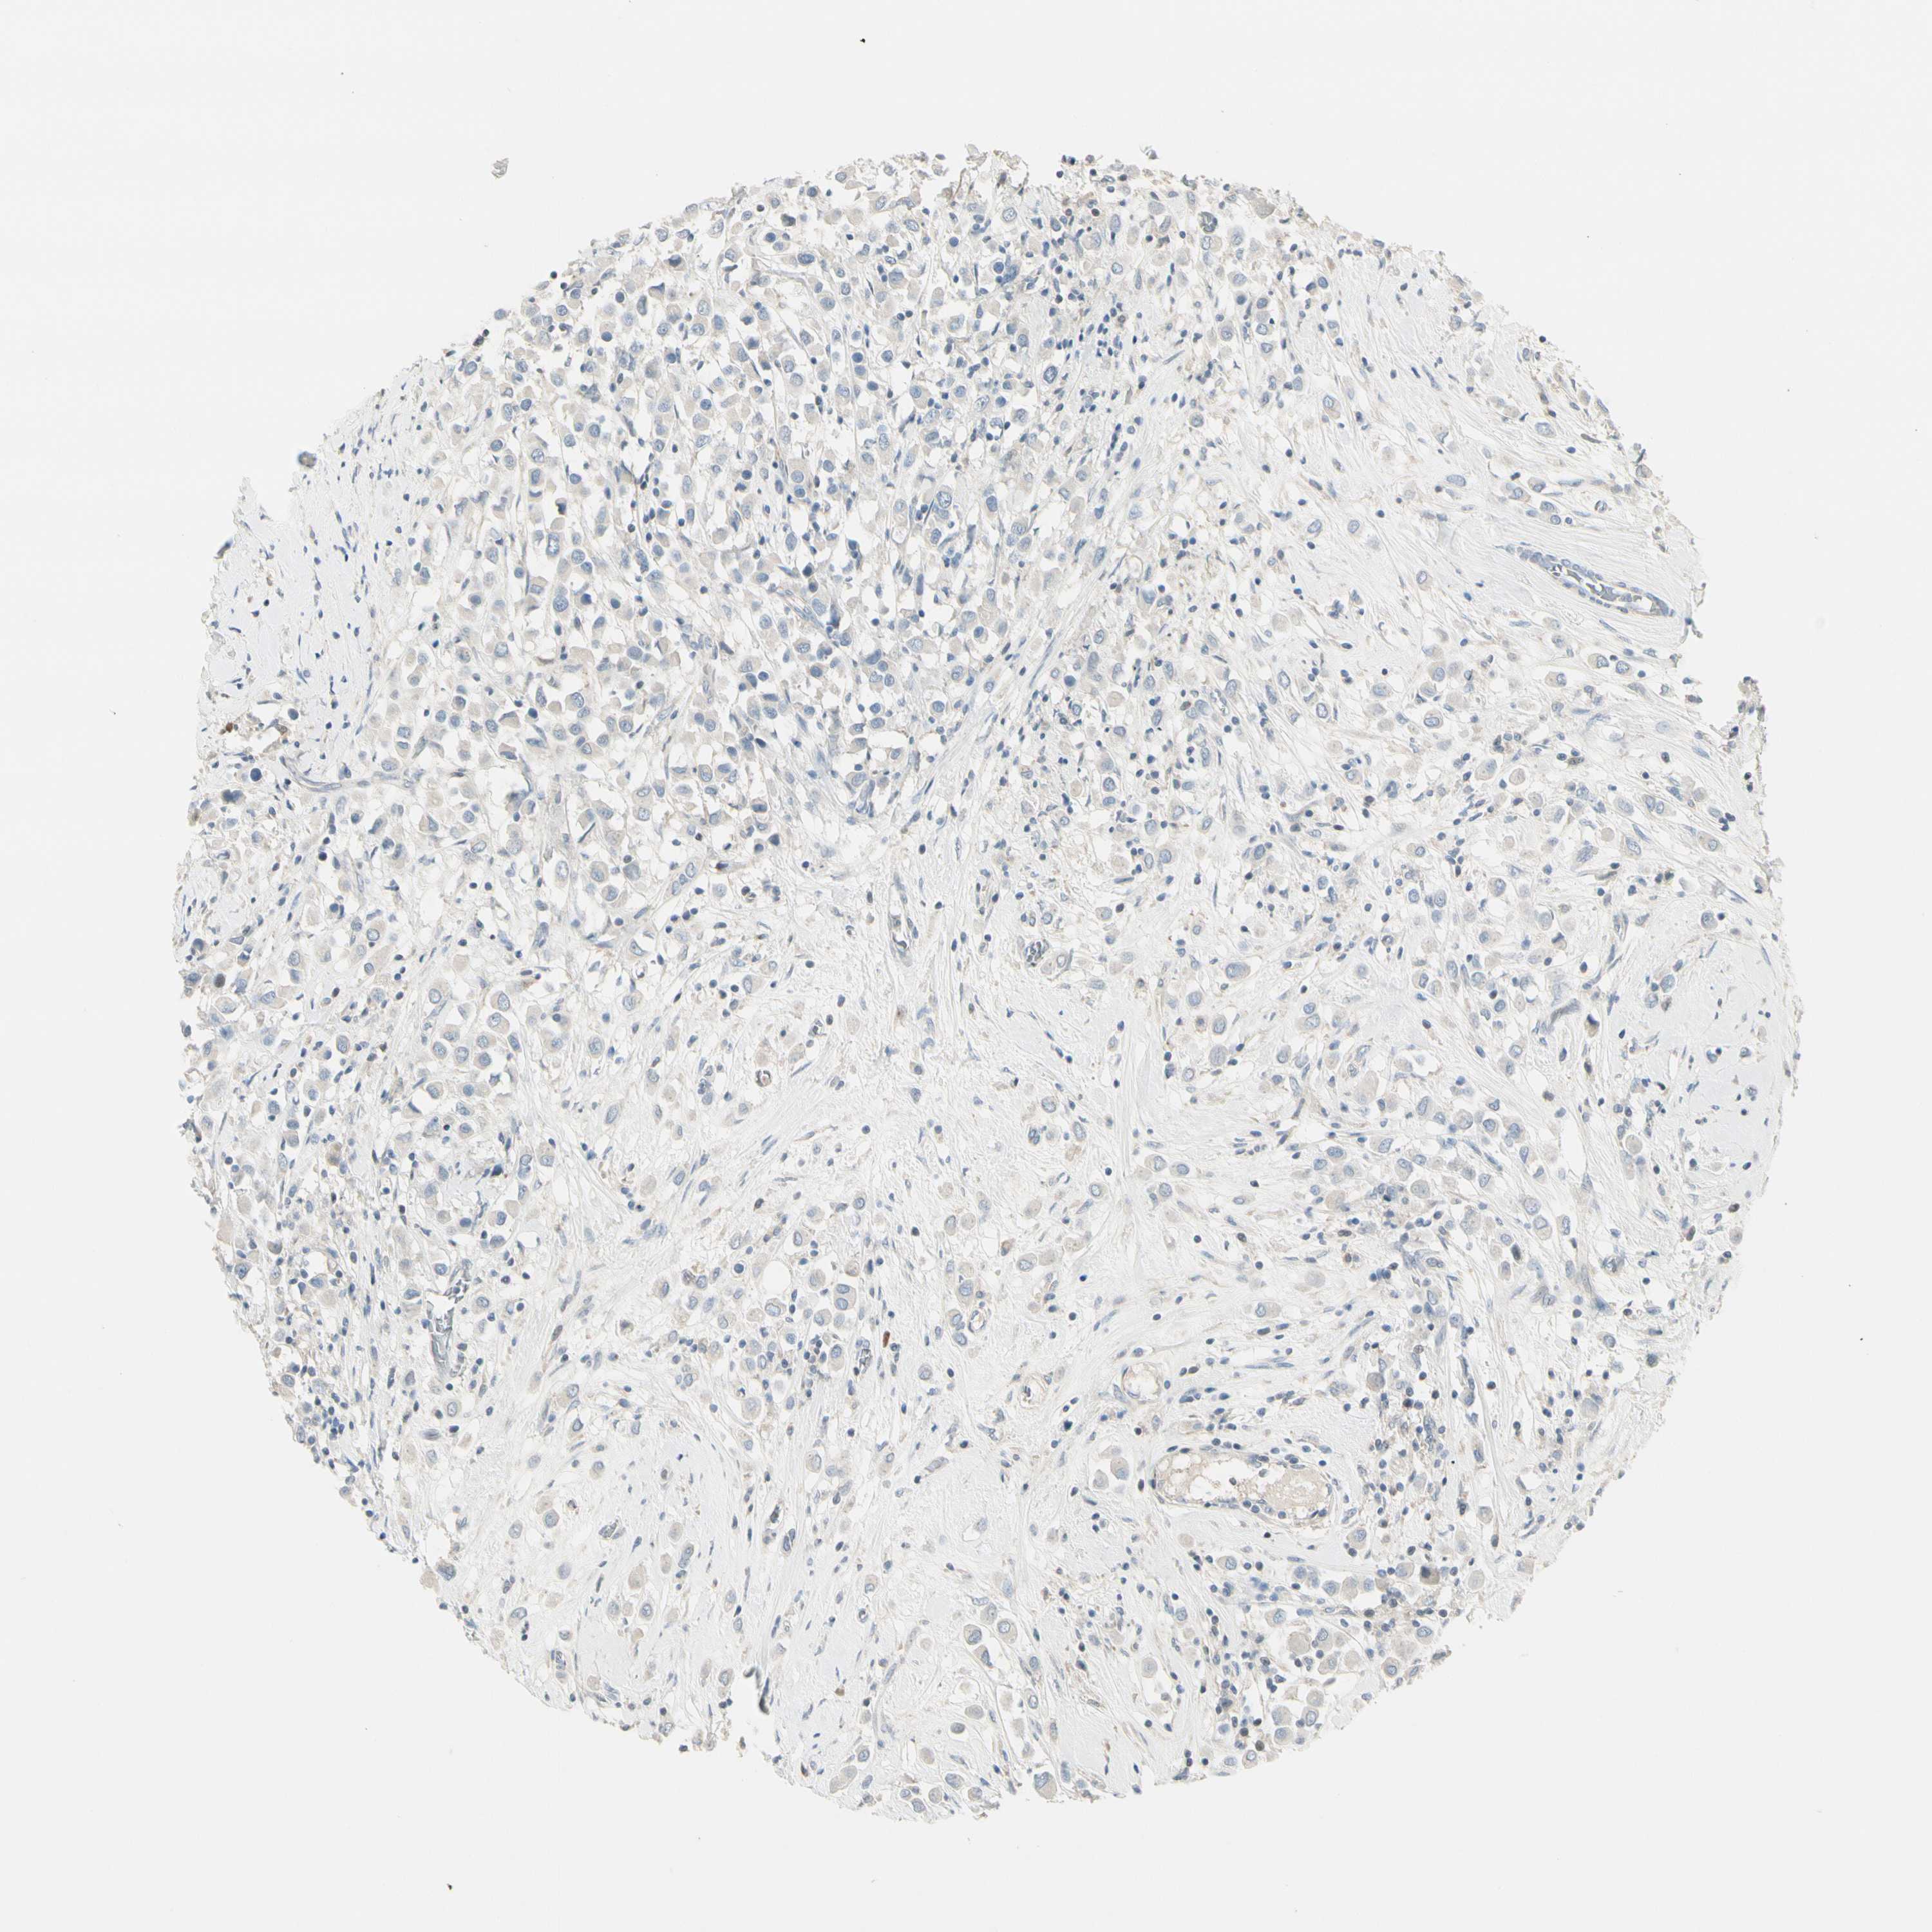

BRCA TCGA BRCA VALIDATION PROTEIN EXPRESSION

ANTIBODIES

AND

VALIDATION